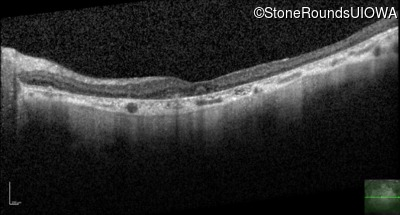

Optical Coherence Tomography - Left - 10/125 sc

Exemplar / OCT Stack

OCT Stack